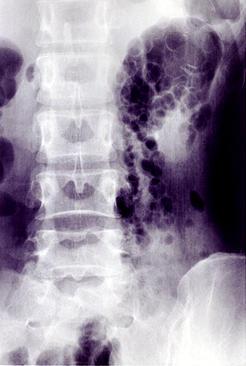

腸管のう胞性気腫症の腹部単純x線像  立位による腹部単純写真です。患者の左上腹部に、1~3cm大の円形の陰影が丁度、ブドウの房状、シャボン玉の泡のように集合して認められます。

疾患(病理主体)の分類腫瘍様病変/腸管嚢胞性気腫症

部位(臓器別)大腸/S状

検査方法X-P

病変の最大径(ミリ)30〜34